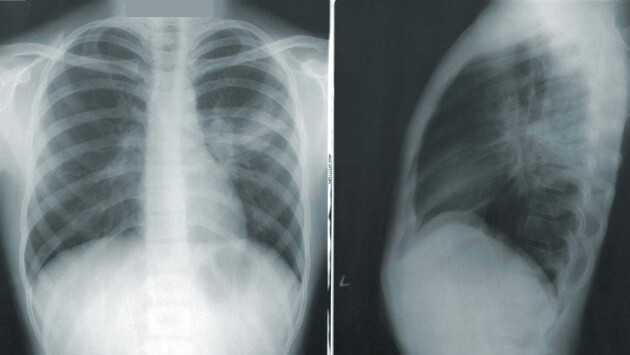

«В России около 10% из 1,3 - 1,4 млн малышей рождаются недоношенными. Зачастую это вызывает бронхолегочную дисплазию - хроническое заболевание, при котором легкие формируются неправильно. У большинства детей с таким недугом в будущем возрастает риск возникновения респираторных инфекций, синдрома бронхиальной гиперреактивности и других проблем со здоровьем. На сегодняшний день существуют методы прогнозирования заболевания, но все они основаны только на одной группе параметров, например, на результатах лабораторного исследования пуповинной крови. Проблема в том, что они не включают в себя многие факторы, которые воздействуют на развитие болезни», — сообщили в университете.

По данным исследователей, бронхолегочная дисплазия - самое частое хроническое заболевание легких у недоношенных новорожденных детей с критично низкой массой тела. Оно связано с незрелостью легочных тканей, токсичным воздействием кислорода при искусственной вентиляции легких и рядом других факторов. Задача врачей в этом случае - подобрать лечение, которое снизит риск развития серьезных форм болезни. Поэтому ученые Пермского политеха разработали математические модели, которые учитывают количественные показатели из разных групп характеристик, влияющих на степень тяжести заболевания: вес при рождении, питание, характеристики аппарата искусственной вентиляции легких.